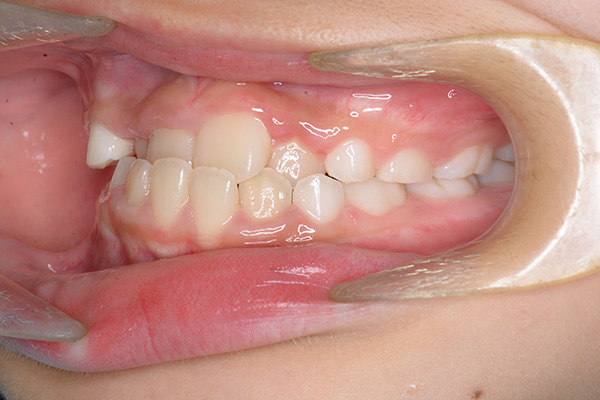

動的治療開始前(9歳7ヵ月)

動的治療開始前

(9歳7ヵ月)

口腔内所見 over jet -2.5mm、over bite 2.0mm、大臼歯関係はⅠ級 。Hellmanのdental ageはⅡCであり前歯部は反対咬合を呈していた。